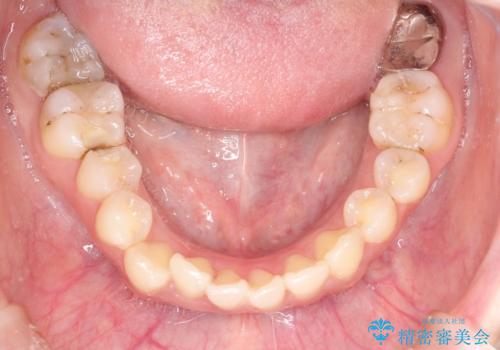

八重歯をインビザラインで非抜歯矯正

- 八重歯を主訴に来院されました。

インビザラインにて奥歯を後方に移動して八重歯が入るスペースを確保してく矯正する計画としました。

八重歯と前歯のガタガタがなくなり、歯並びがきれいになったのと、かみ合わせも改善することができました。